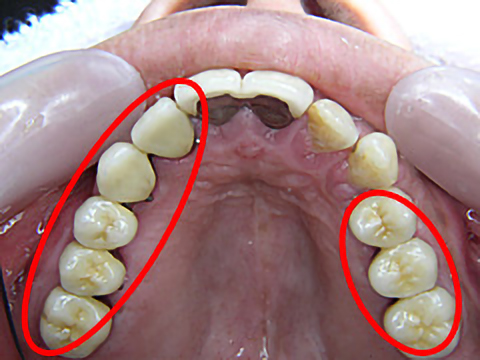

症例3

年齢 | 42歳 |

---|---|

性別 | 女性 |

費用 | 1本あたり330,000円+保険で必要な金額(抜歯など) |

治療期間/治療回数 | 1年半/20回 |

治療におけるリスク |

骨の状態により治療ができない場合があります。 一度埋め込んだインプラントが脱離する可能性があります。 上部構造は消耗品です。一生持つものではなく、破折する可能性があります。 |

歯科治療が怖くて長きにわたりお口を放置されていましたが、一大決心の後、当院にて治療を受けられました。

右上4本、左上も3本、抜歯即時埋入を含めてインプラント治療を受け、噛み合わせを取り戻すことができました。また、下顎の前歯も大きくすり減っていたため、オールセラミックスで治療しました。